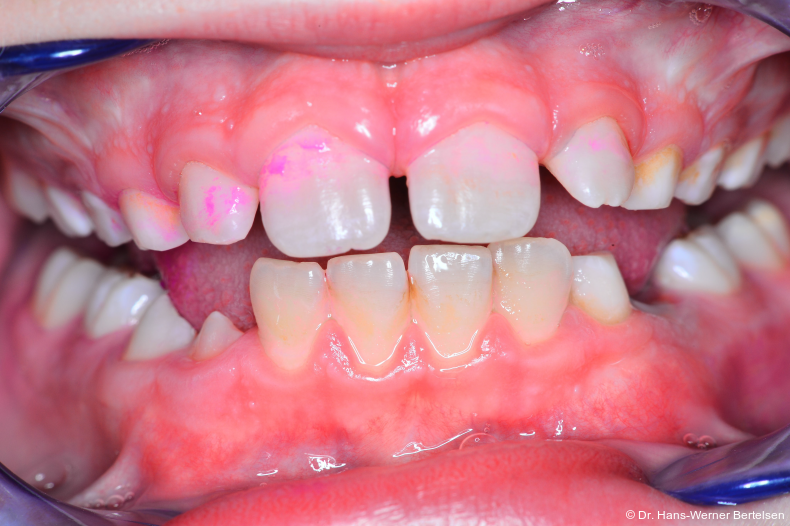

Erst die fotografische Dokumentation des Mundhygienestatus brachte den entscheidenden Durchbruch. „One size fits all“, das bekannte Prädikat aus dem stationären Sockenhandel, trifft in der Zahnarztpraxis leider bekanntlich nicht zu. In Bezug auf die Compliance der so wichtigen Anleitung der Zahnpflege kommen wir in unserer ­Praxis mit der hier beschriebenen Technik doch sehr nahe an eine 100%ige Quote heran. Es ist jedes Mal aufs Neue spannend und faszinierend, wenn sich bereits achtjährige Kinder darauf freuen, ihre erlernten Putzerfolge in der Praxis vorzuführen, um dann am Monitor gemeinsam mit der ZMF oder mir ihre tollen Ergebnisse zu bestaunen. Mitarbeit, Selbstwirksamkeit und Lob sind Garanten für eine gelungene Prävention und ersetzen Ermahnung, Frustration und Unverständnis.

Ein Bild sagt mehr als tausend Worte

Wie im Leben, so auch hier - die Fotodokumentation erspart uns nach einfacher Implementierung in den Verlauf der Prophy­laxe sehr viel Zeit. Zeit, die wir mit allen vorherig angewandten anderen Mitteln und Techniken regelmäßig vergeudet hatten. Aber es gibt noch weitaus mehr Vorteile, sowohl für die Praxis als auch für die Kinder und Eltern. So lässt sich die Motivation für einen Folgetermin durch die Ankündigung eines weiteren Fototermins sehr gut erlangen. Gleichzeitig steigt bei einer sichtbar nachgewiesenen Verbesserung der Zahnpflege mit der Laune auch der Ehrgeiz unserer kleinen Patient/-innen, uns bei Folgeterminen wieder mit einem guten Ergebnis zu überzeugen. Sehr selten nur beobachten wir an dem Folgetermin einen Rückschritt. Das einmal erzielte Putzergebnis erweist sich in der Regel als erlernt und damit sehr stabil. Zudem ist es die beste Gelegenheit, für den Einsatz von Plaque-Färbe­tabletten zu werben. Es ist schon erstaunlich, wie wenig An­wendung dieses wertvolle und aus meiner Sicht schier un­verzichtbare Hilfsmittel in der Bevölkerung findet. Die Ver­fügbarkeit von Plaque-Färbetabletten ist in der Lernphase sehr viel wichtiger als die Marke der Zahnpasta.